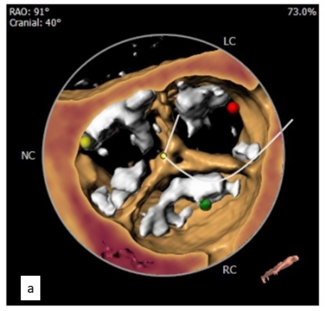

Rajat Datta, MD, DM; Vivek Singh Guleria, DM; G. Keshavamurthy, DM; K.J. Ratheesh, DM; Prashant Bharadwaj, DM

The authors present a case report where a deployed valve popped out due to underexpansion.